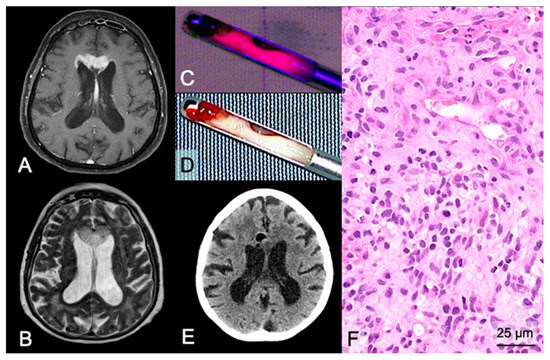

In the case of biopsy, 5-ALA was used for intraoperative visualization of diagnostic tumor tissue in 92 (86%) stereotactic/open biopsies. Of these, 5-ALA fluorescence was capable of visualizing tumor tissue in 91 cases (99%). In detail, 83 (90%) cases showed strong fluorescence and 8 (9%) cases vague fluorescence as maximal fluorescence level. An illustrative case is provided in Figure 3. It is of note that the only case (open biopsy) with an absence of visible fluorescence showed massive necrotic/hemorrhagic features with only rare tumor cell infiltration of a GBM.

Figure 3. Case illustration of a stereotactic biopsy using 5-ALA fluorescence in a suspected GBM. (A) Preoperative MRI demonstrates a lesion in the midline/corpus callosum in the frontal lobes with contrast-enhancement on T1-weighted sequences and (B) hyperintensity on FLAIR sequences of a 70-year-old female patient. (D) During stereotactic biopsy, the neurosurgeon checks the collected tissue sample of the target region with significant contrast-enhancement under the sterile neurosurgical microscope using white-light and (C) violet-blue excitation light to investigate the fluorescence status revealing strong fluorescence. (E) Postoperative CT shows no hemorrhage in the biopsy area, and the air bubble indicates the correct biopsy site of the obtained tissue samples. (F) Histopathological analysis reveals a glioblastoma WHO grade IV.